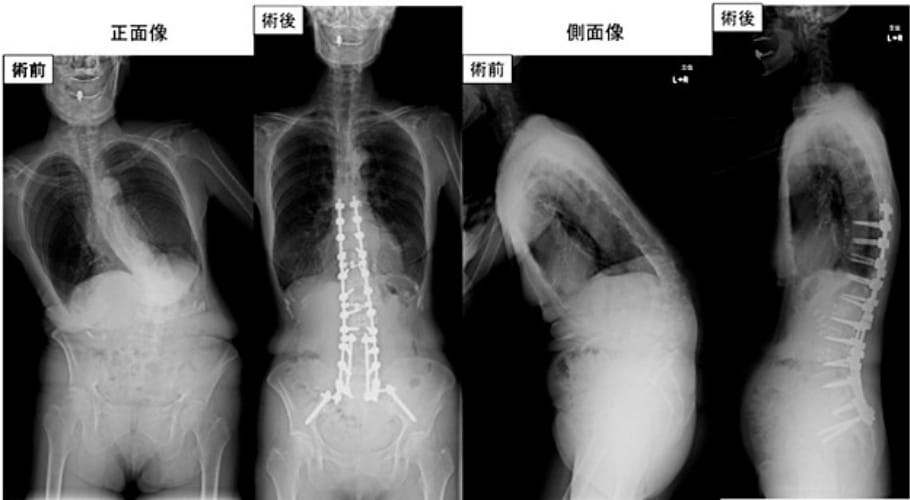

特発性側弯症では、コブ角が45度以上の場合、カーブが進行することが知られており、手術の適応となります。当院では、CTナビゲーションシステムを用いて正確かつ安全に椎弓根スクリューを挿入し、脊髄モニタリング(経頭蓋刺激-筋誘発電位モニター:Br-MEP)を行い、神経麻痺を予防しています。2019年12月よりCoPlanar法を導入しており、この方法は凸側の椎弓根スクリューを通じて椎体軸を同一平面に整列させ、3次元的な矯正を行う技術です。